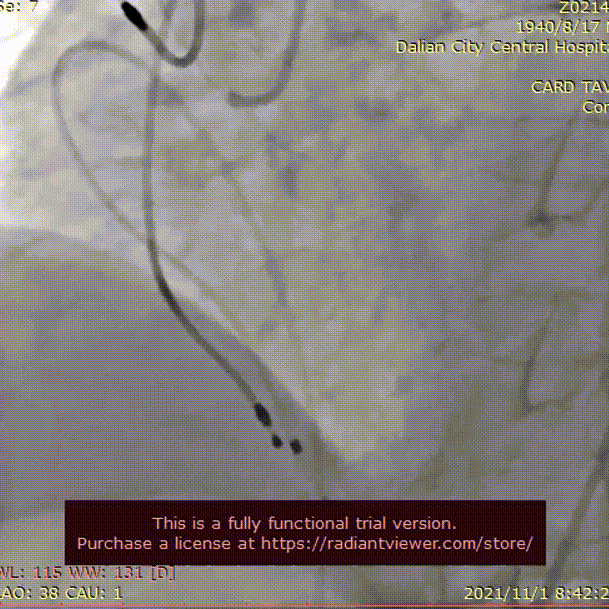

术中影像

22mm球囊充分扩张

瓣膜初始定位, 选择0位释放

TaurusElite AV26mm瓣膜,瓣上2mm 工作位造影

瓣膜形态良好 位置理想